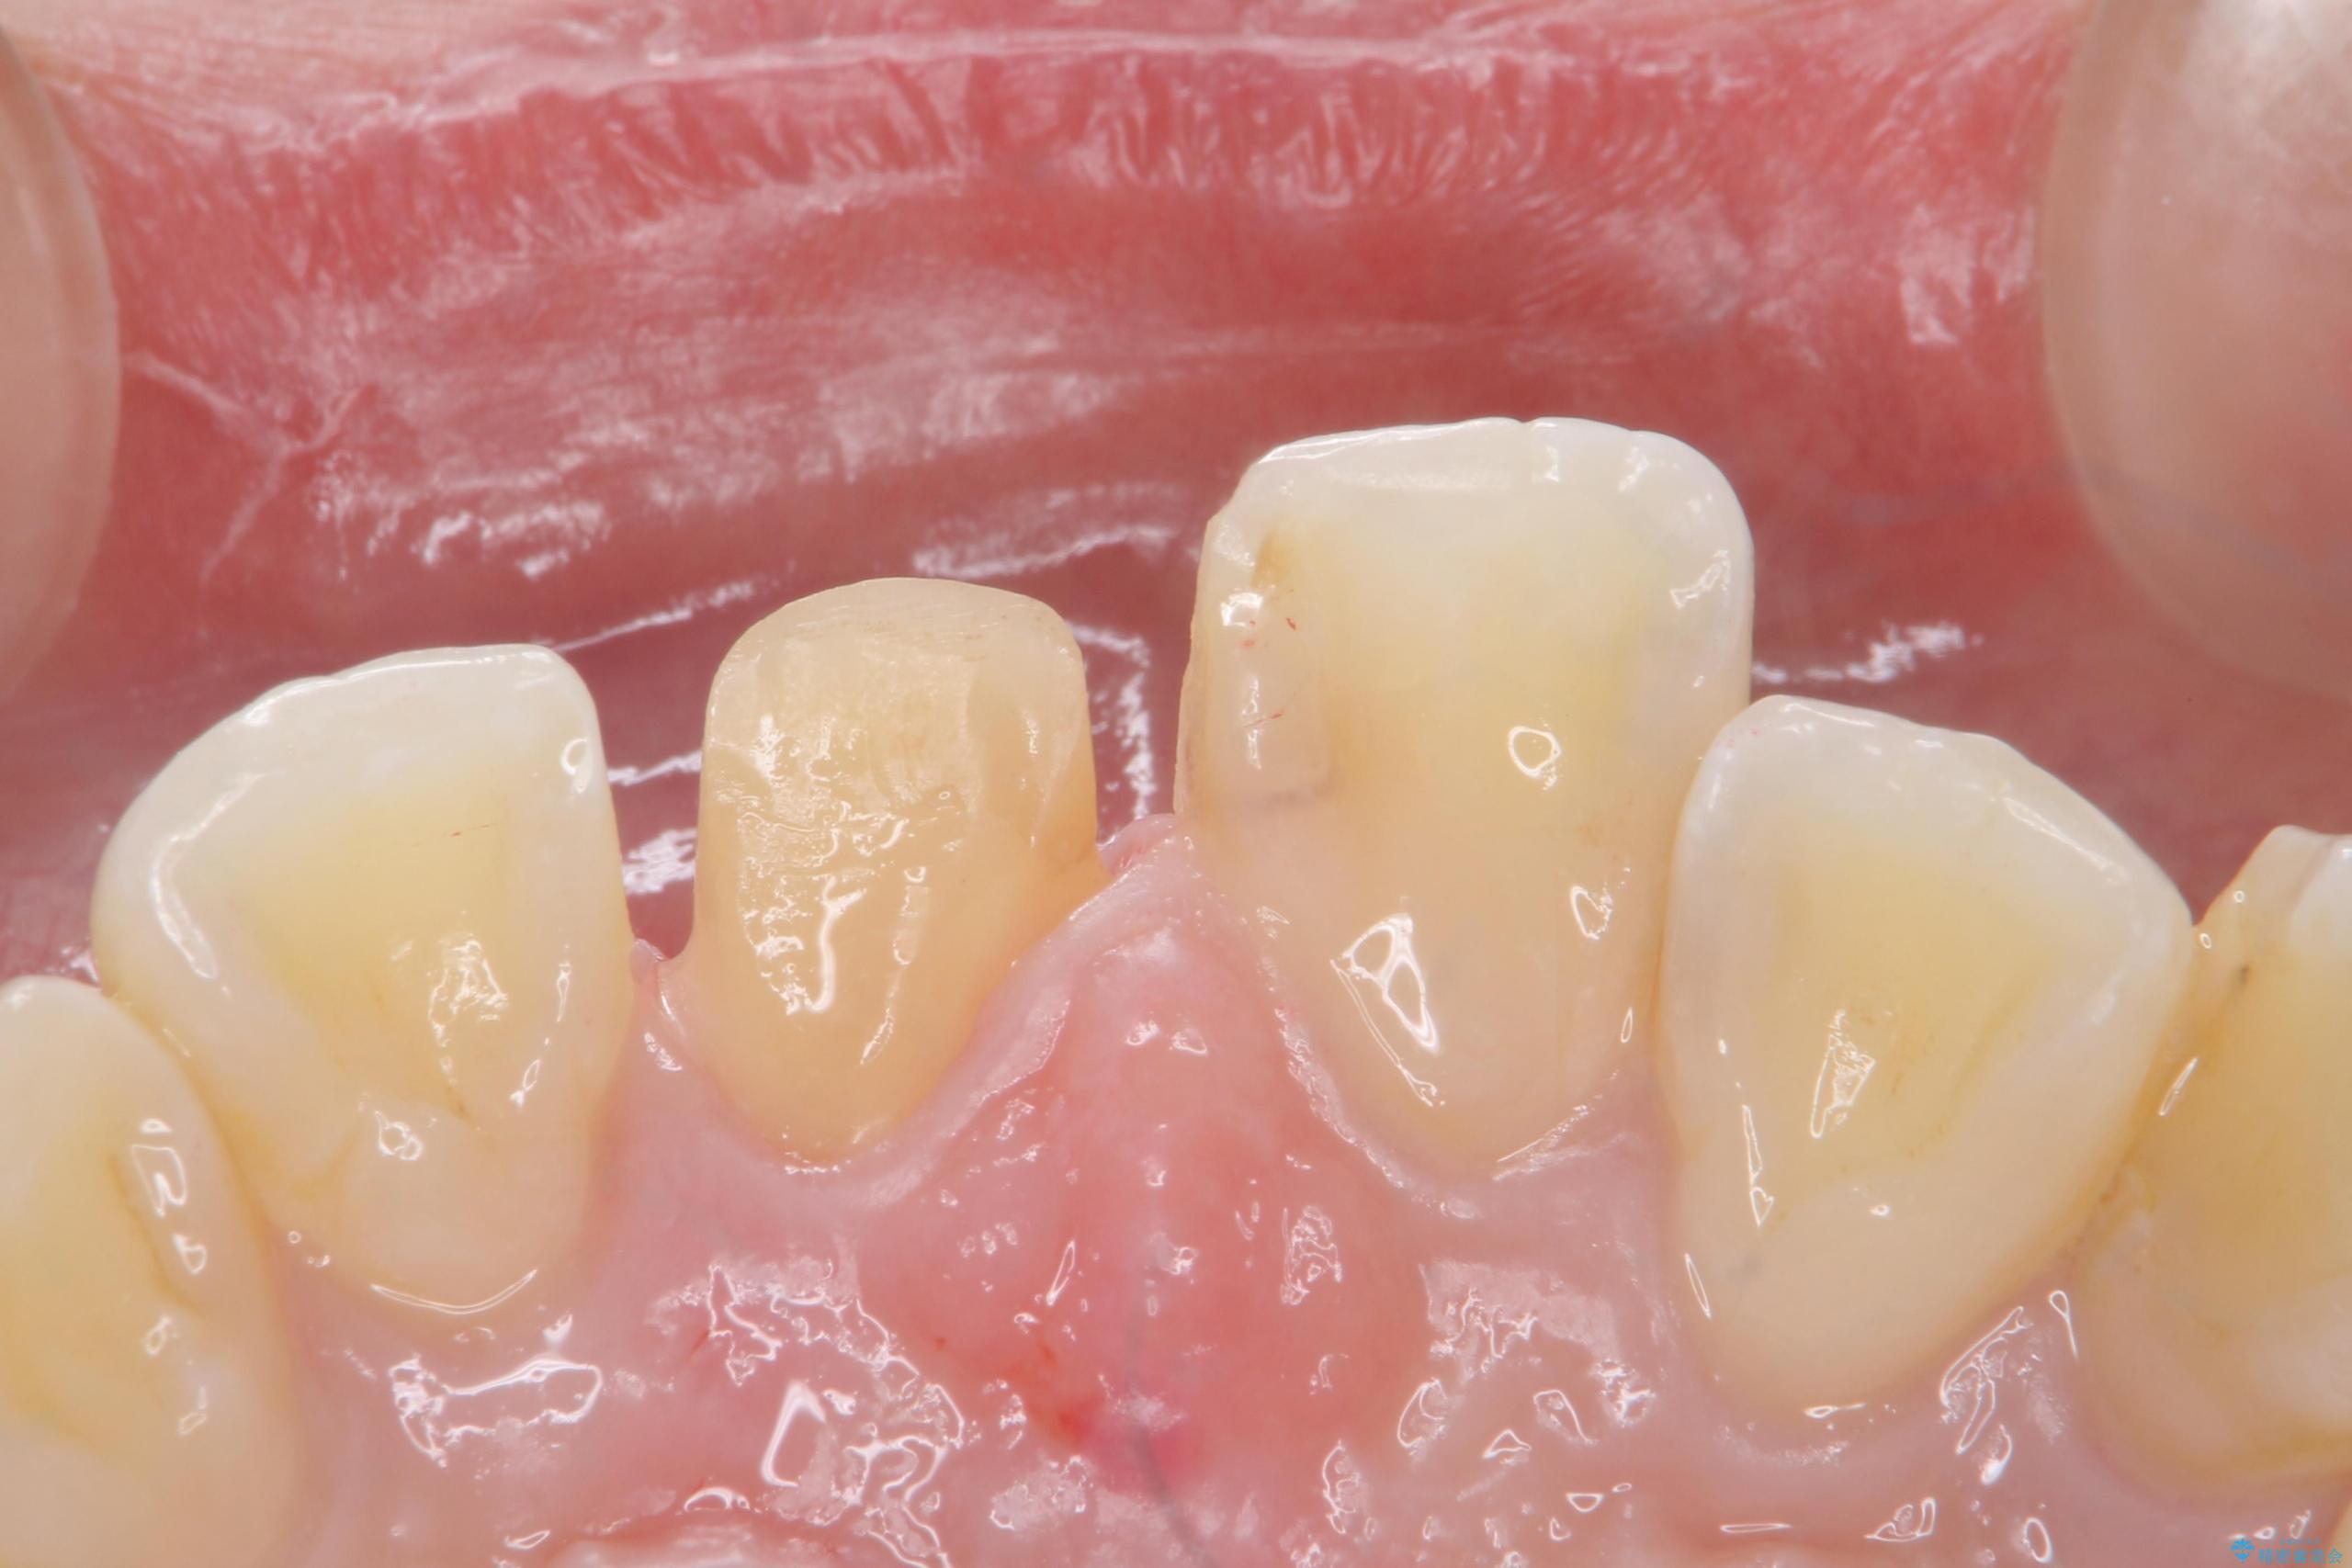

- 前歯のかぶせ物の色が気になるとのことで来院された患者様です。

セラミッククラウンで作り変えていきます。